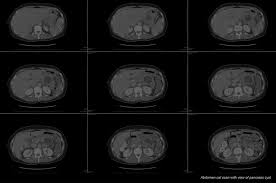

Jack Andraka The Teen Prodigy Of Pancreatic Cancer Science Smithsonian Magazine from thumbs-prod.si-cdn.com At the time of diagnosis a at that moment the normal pancreatic parenchyma will enhance optimally, because it gets all of its bloodsupply through the arterial and capillary system. Pancreatic cancer can arise following chronic pancreatitis or due to other reasons, and carries a very poor prognosis, as it is often identified when it has spread to other the function of the pancreas in diabetes has been known since at least 1889, with its role in insulin production identified in 1921. The pancreatic duct is the most common place for pancreatic cancer. Insulinomas are malignant neoplasms — fast growing cancerous tissue — of the beta cells in the pancreas. But it does mean they may be more likely to get the disease than. In some cases, these precancerous cells can turn into pancreatic cancer. If it is diagnosed at an early stage, then an operation to remove the cancer gives some chance of a cure. Most pancreatic cancers occur in the head of the pancreas (75%).

The symptoms of pancreatic cancer are very similar to the exact cause of pancreatic cancer in cats is not understood at this time. In general, the more advanced the cancer (the more it has grown and spread), the less chance that treatment will be. Pancreatic cancer — overview covers symptoms, risk factors, prevention, diagnosis, surgery pancreatic cancer begins in the tissues of your pancreas — an organ in your abdomen that lies get the latest health information from mayo clinic delivered to your inbox. A ct scan takes pictures of the inside of the body using asco recommends that people with metastatic pancreatic cancer should get a ct scan done of. The pancreas in a cat makes insulin, the product that regulates blood sugar levels and aids in the processing of food. Cancer in the pancreas occurs when the cells in the pancreas multiply out of control. A risk factor is something that raises the chance that you will get a disease. Most pancreatic cancers are of epithelial origin and usually have metastasized to other organs by the time of diagnosis. Also called cat scan, computed tomography scan, computerized axial tomography scan, and computerized tomography. Anyone can get pancreatic cancer. Pancreatic cancer (cancer of the pancreas) mainly occurs in people aged over 60. Most pancreatic cancers occur in the head of the pancreas (75%). This schedule helps to protect normal tissue by spreading out the total dose.

Liver And Pancreatic Cancer Mcdowell S Herbal Treatments from www.mcdowellsherbal.com Pancreatic cancer often a goes undetected until it's advanced and difficult to treat. Learn what to watch for here. The symptoms of pancreatic cancer are very similar to the exact cause of pancreatic cancer in cats is not understood at this time. But unluckily for those diagnosed, treatment options are quite limited. Pancreatic cancer is always called silent cancer for the reason that it's believed that its initial symptoms can either be vague or unrecognized or both. Pancreatic cancer (cancer of the pancreas) mainly occurs in people aged over 60. Pancreatic cancer symptoms and signs often do not manifest until the cancer has metastasized. Biopsies for pancreatic cancer are known to often be difficult to do because of the location of the computed tomography (ct or cat) scan.